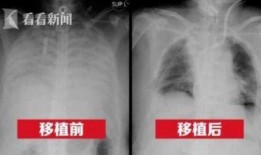

最近港媒可是爆出了一个大新闻,让人不禁瞪大了眼睛!说的是新冠肺病人的一些最新情况,听起来是不是有点刺激?那就跟着我一起,来揭开这...